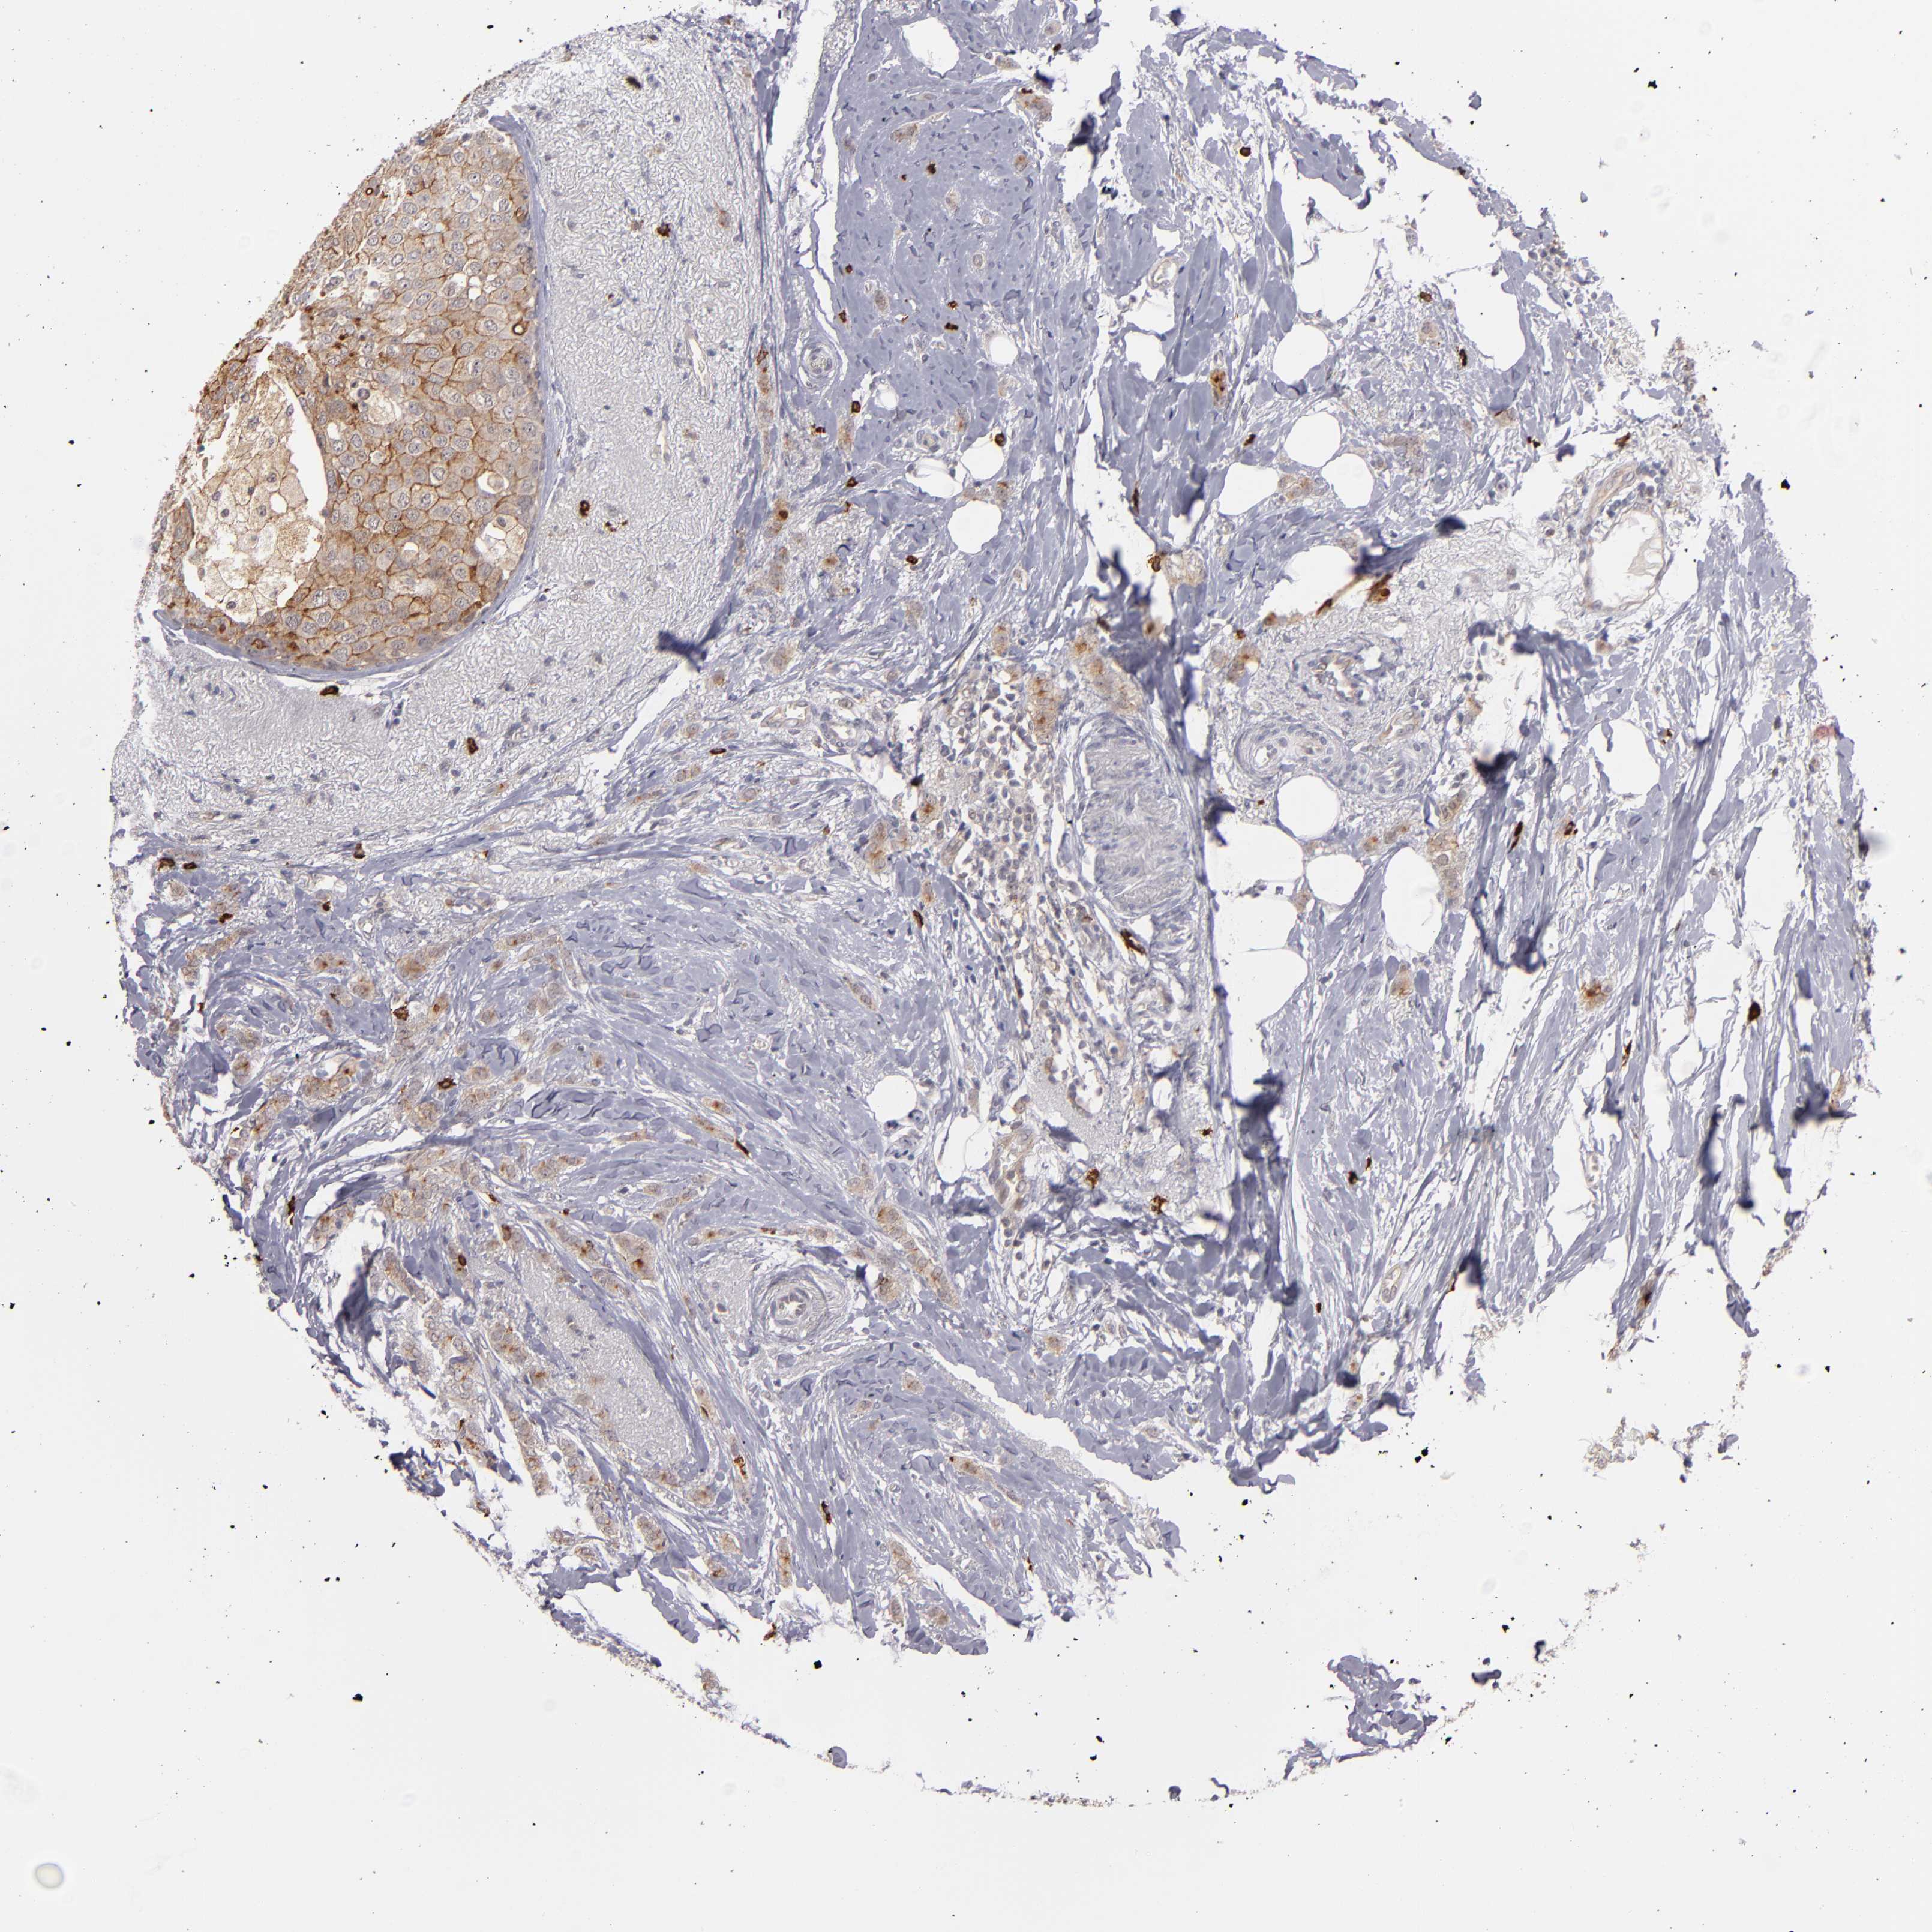

CANCER BREAST CANCER Show tissue menu

BRCA TCGA BRCA VALIDATION PROTEIN EXPRESSION

ANTIBODIES

AND

VALIDATION